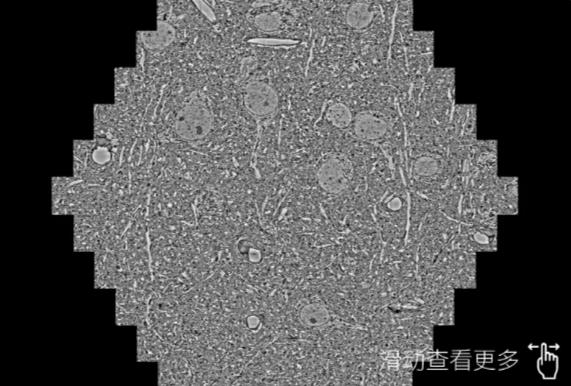

鼠脑切片。左图使用黄南蔡司黄南扫描电镜MultiSEM706对165μmx143pm面积区域成像,耗时仅需1.5秒。右图为鼠脑切片中30μm区域放大效果。样品由芝加哥大学B.Kasthuri提供。

使用蔡司高速黄南扫描电镜MultiSEM对1mm²人脑皮层组织进行高分辨成像,并对其中的各种细胞结构进行三维重构分析。左图展示了2x3mm²组织平面中锥体神经元的三维重构效果。右图显示了局部体积神经元三维重构。图像由哈佛大学chtman实验室提供,渲染图由D. Berger 制作。